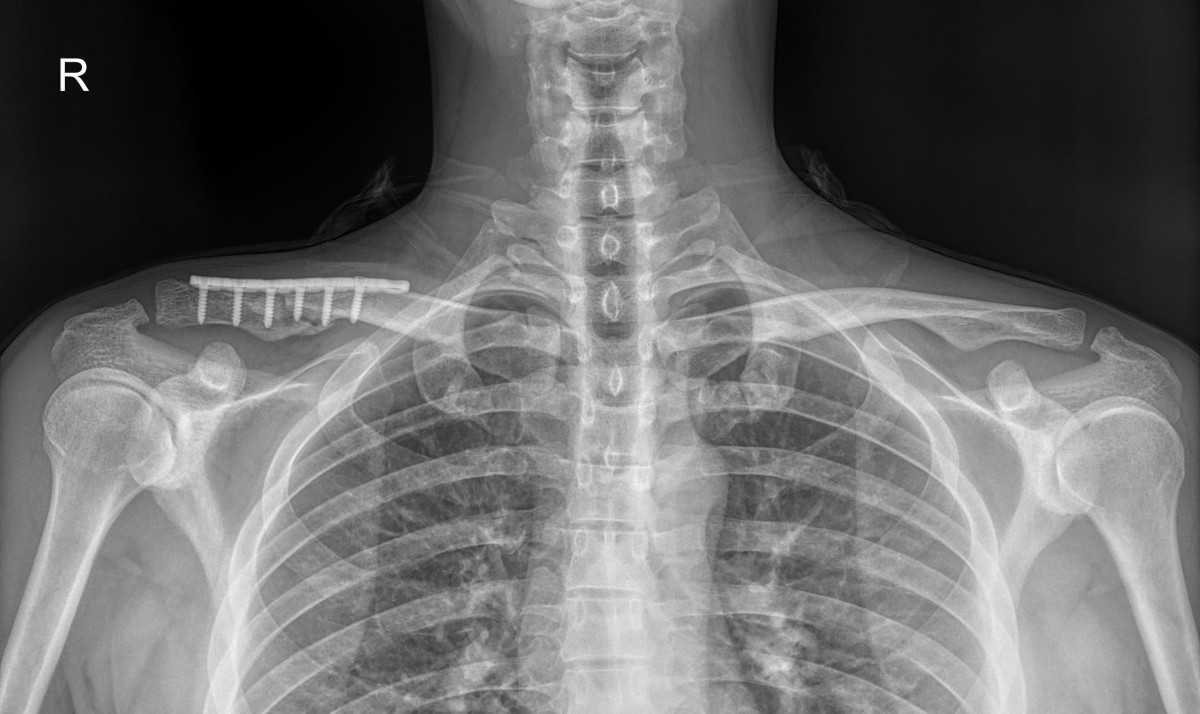

이재상 원장님 쇄골 골절 수술 신종O 환자

d4279b3b94d98ed627b1644855bcf9f2_1699601025_9941.jpg

d4279b3b94d98ed627b1644855bcf9f2_1699601040_0474.jpg